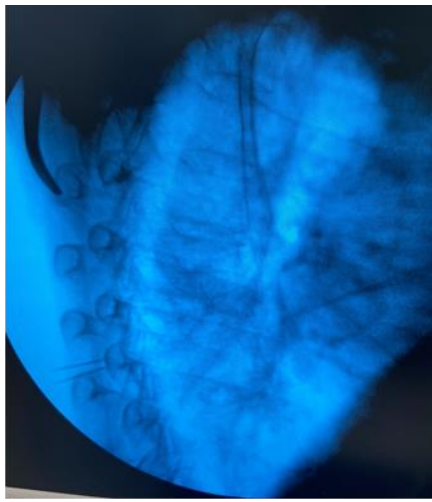

Pre anesthestic checkup was done and consent taken before the procedure. Patient was positioned in the prone position with a pillow underneath the chest and arm by the side. Standard anesthesia monitors were applied. Fluoroscopy was used to identify the right level, counting up from the 12th vertebral body. Target was the supero-lateral aspect of the Transverse process of the vertebra, for the radiofrequency ablation of the medial branches. Adequate caudal and contralateral oblique tilt was given to position the fluoroscope beam parallel to the targeted nerve. 20 G, 10 cm RF cannula ,10 mm curved tip (Boston scientific, USA), were advanced to the target sites in a parallel manner after anesthetizing the skin by lidocaine 2%. (Fig 2) Another two RF cannuale were inserted at T8 and T9 levels in a similar fashion. True lateral views were taken to ensure proper depth of all needles (Fig. 3). The stylets were withdrawn and radiofrequency probes were inserted. At all levels, sensory stimulation at 0.5 V, 50Hz and motor stimulation at 2 Hz up to 1.5 V/2V were obtained.  After Iv sedation, two Radio-frequency lesions were done at 80 degrees Celsius for 90 seconds 2mm apart. 10 mg of methylprednisolone in 1ml lidocaine 2% was injected ta each level to prevent post-ablation neuritis. The same procedure was repeated at the same levels on the other side.

Fig 2 - RF needle placement over the super-lateral aspect of the Transverse process.